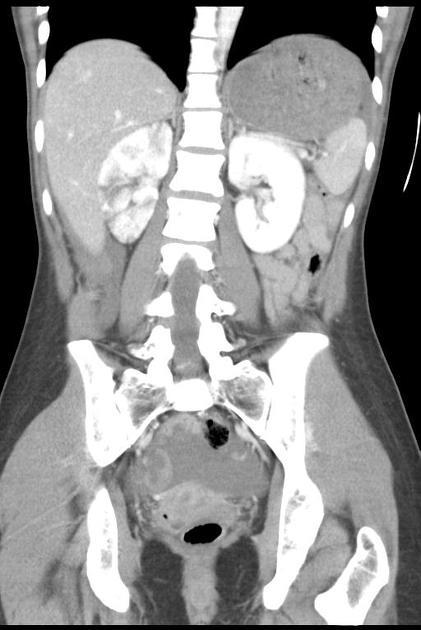

54F with abdominal pain, n/v

Closed loop obstruction

There is a cluster of fluid-distended loops of small bowel in the pelvis that are notable for relative absence of intraluminal gas, minimal enhancement of their mucosa, infiltrated mesentery, engorged mesenteric vessels and interloop ascites. The distal small bowel is of normal caliber.

—> findings suggestive of ischemia/closed loop include minimal enhancement of the mucosa and engorged mesenteric fat/vessels, and focal ascites.

—> in pt w/appropriate hx could also be a post-op intramesenteric hernia